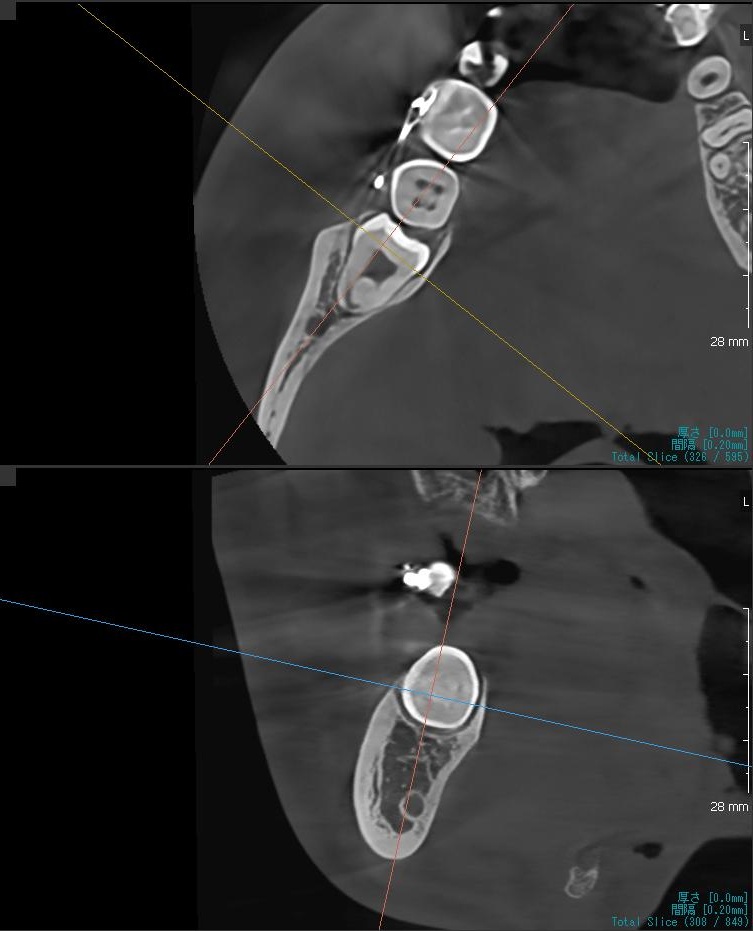

さらに、下顎の親知らずは下歯槽神経に非常に近いところに生えている場合もあるため、CTも撮影し詳しい解析を行います。

親知らずが生えている位置が、神経に近い、あるいは神経に当たっている場合は、大きな病院に紹介する場合もあります。

親知らずの根っこは下歯槽神経から近い距離にありますが、抜歯は可能との診断でした。